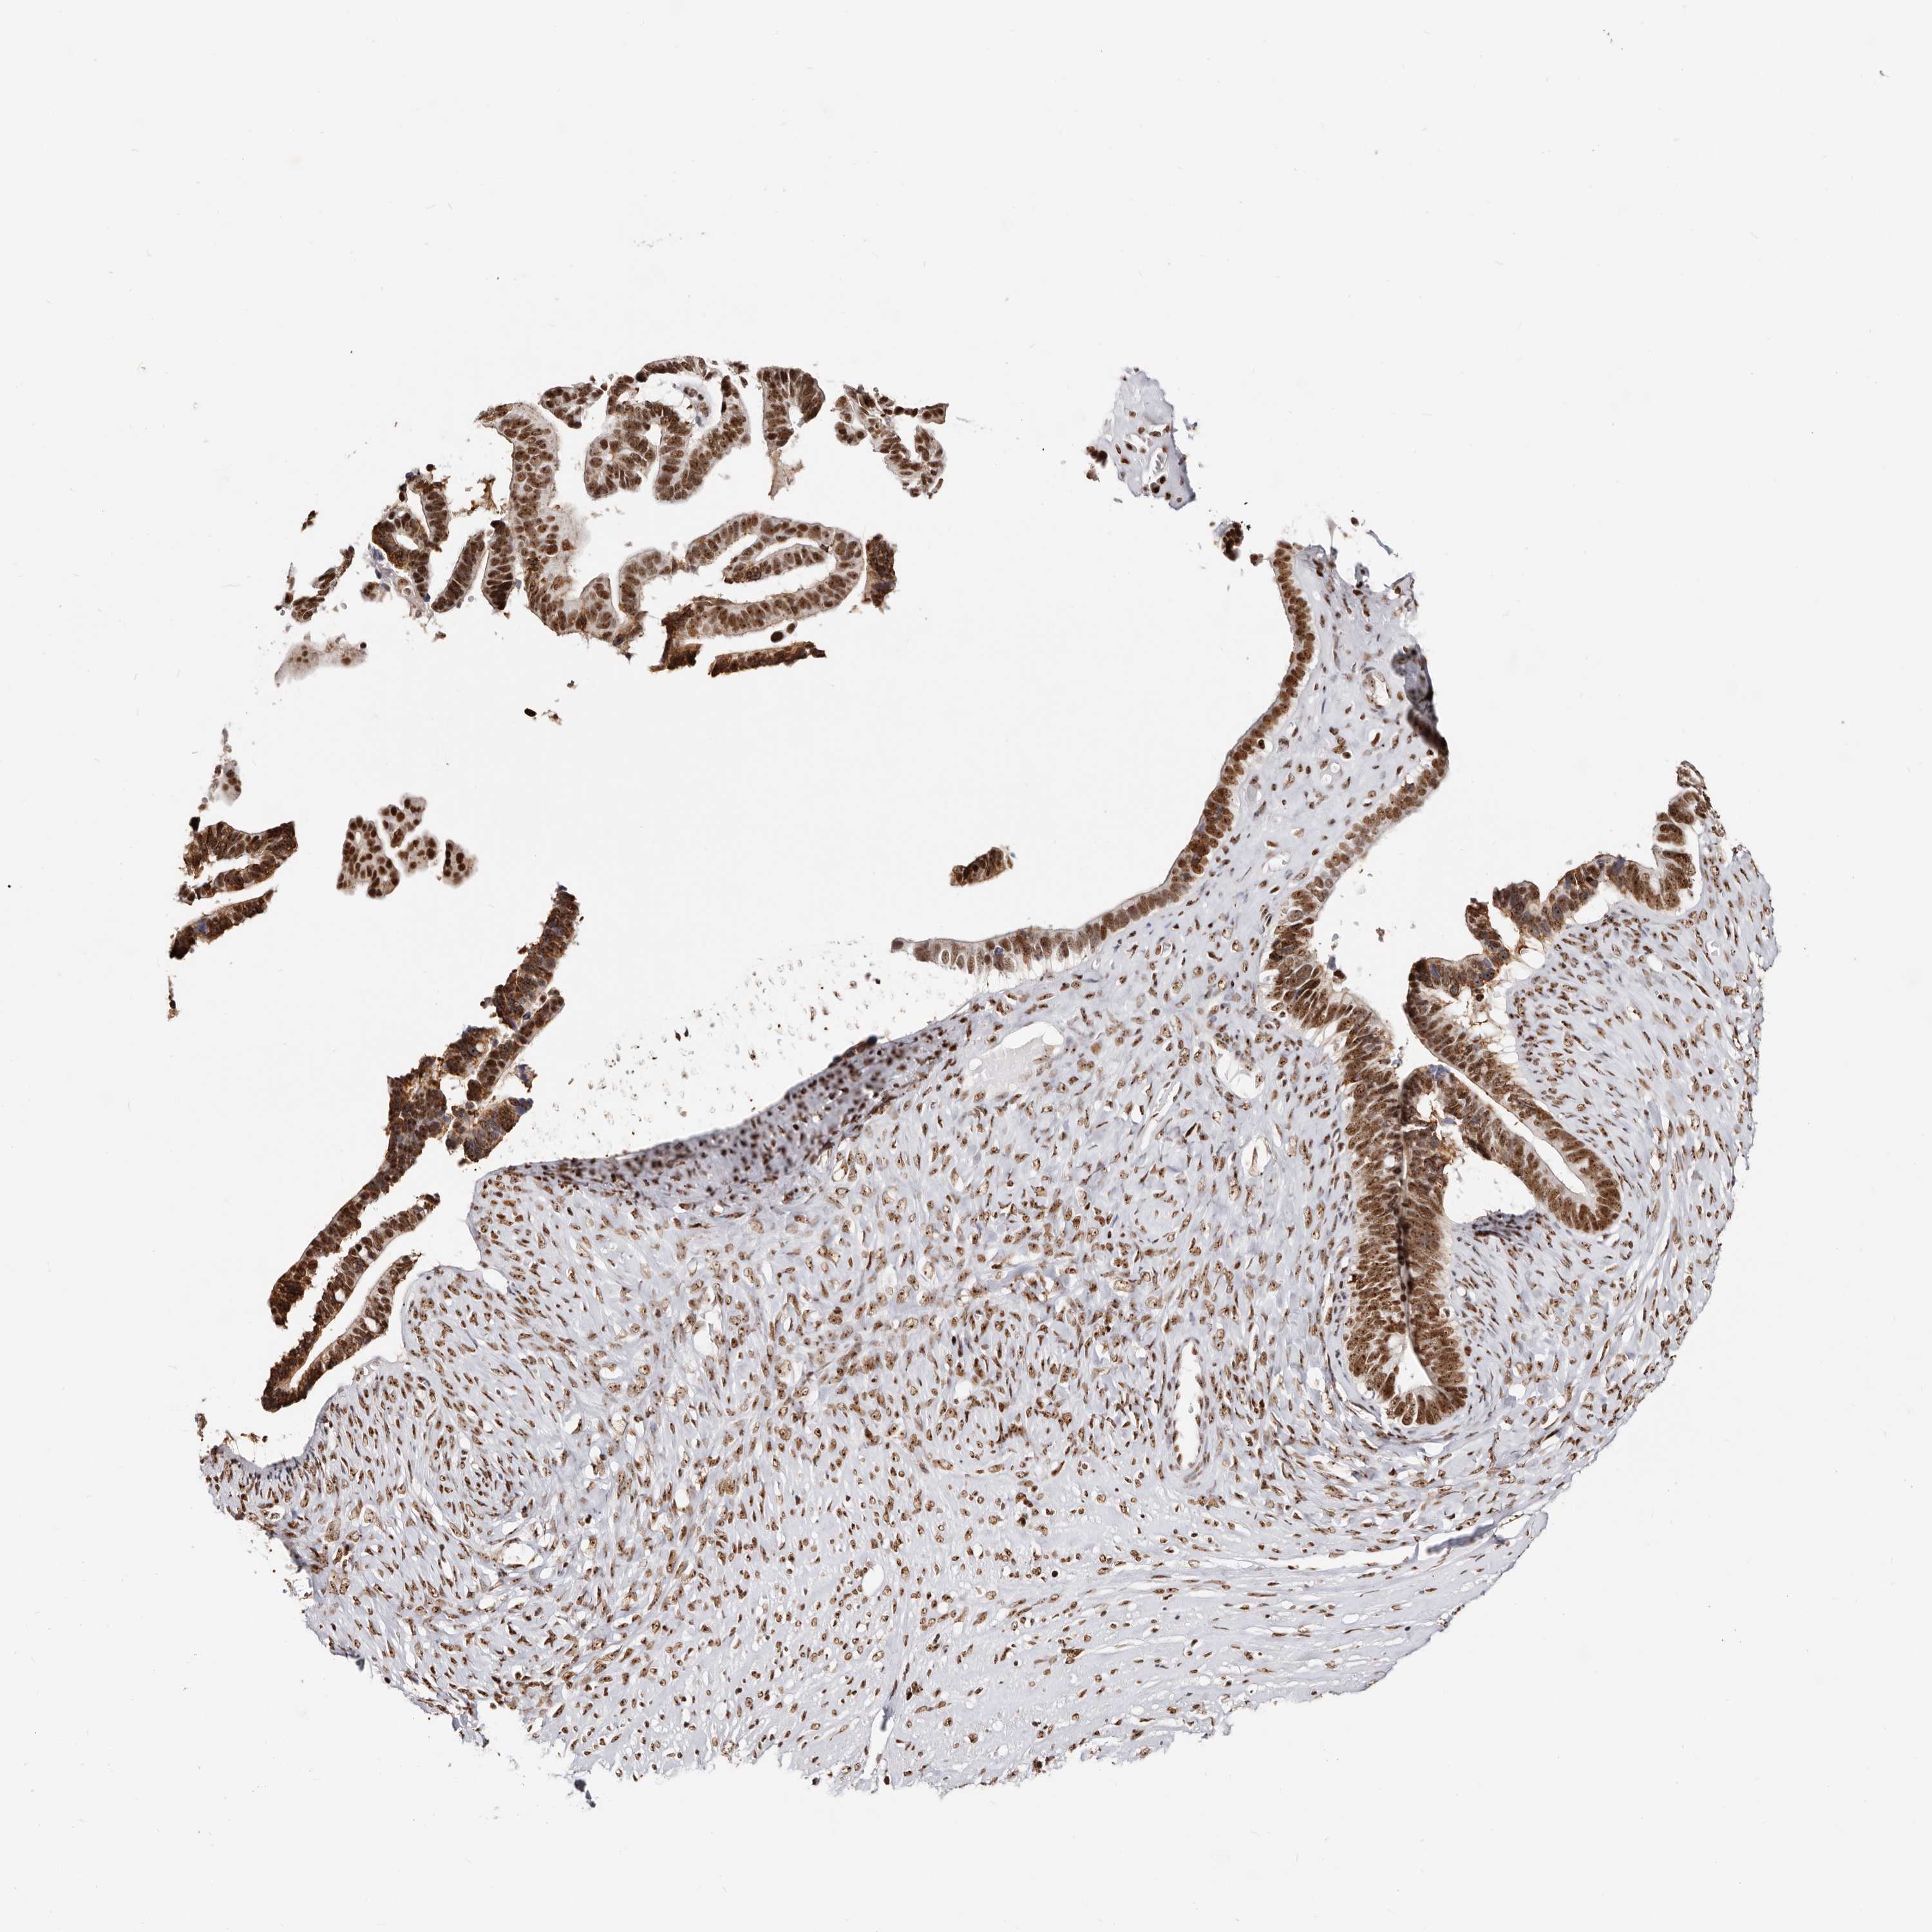

OVARIAN CANCER - Protein expressioni

A mouse-over function shows sample information and annotation data. Click on an image to view it in a full screen mode. Samples can be filtered based on level of antibody staining by selecting one or several of the following categories: high, medium, low and not detected. The assay and annotation is described here.

Note that samples used for immunohistochemistry by the Human Protein Atlas do not correspond to samples in the TCGA dataset.

Antibody stainingi

Antibody staining in the annotated cell types in the current human tissue is reported as not detected, low, medium, or high, based on conventional immunohistochemistry profiling in selected tissues. This score is based on the combination of the staining intensity and fraction of stained cells.

Each image is clickable and will lead to virtual microscopy that enables deeper exploration of all samples and also displays staining intensity scores, fraction scores and subcellular localization as well as patient and tissue information for each sample.

Antibody HPA030142

Antibody HPA030143

Cystadenocarcinoma, serous, NOS

Carcinoma, endometroid

Cystadenocarcinoma, mucinous, NOS

Carcinoma, NOS